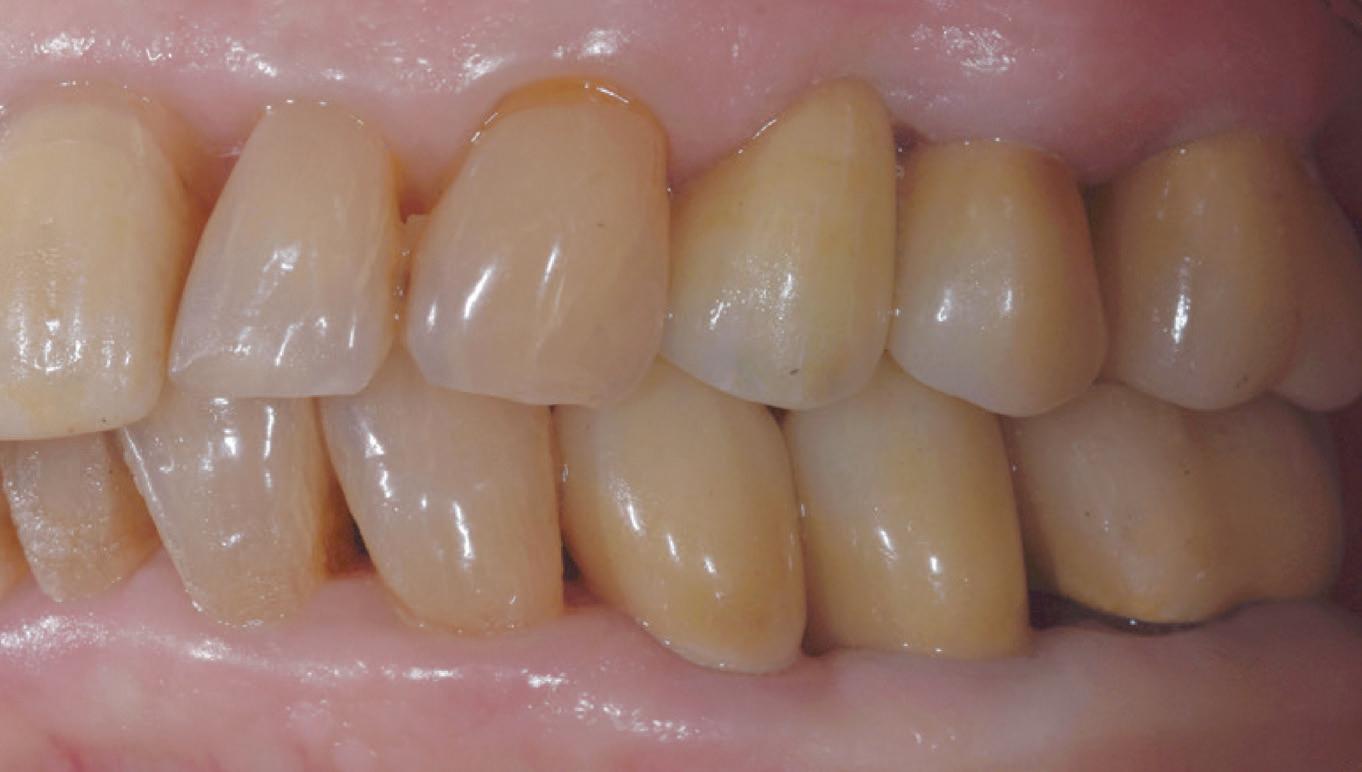

– 5 cavity classes